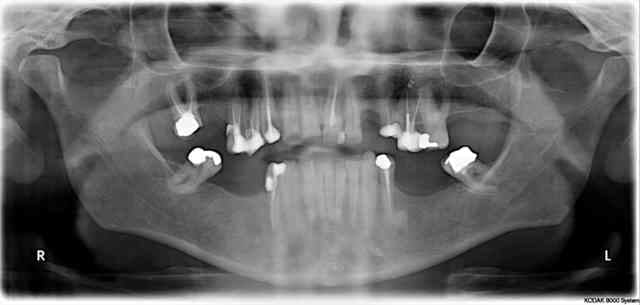

14/04/2011 à 23h02

Avant

Img 9205 mwixzj - Eugenol

Img 9207 pywuvq - Eugenol